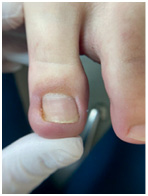

![]() ![]() ![]() Откат в динамике восстановления ногтя после протезирования Вросший ноготь

Самая распространенная и самая сложная работа, с которой мы сталкиваемся. Вросший ноготь причиняет боль, поэтому люди часто боятся обращаться за помощью – представляют себе страшную операцию с длительной реабилитацией. ![]() ![]() ![]() ![]() Работа с вросшим ногтем Одну нашу клиентку внезапная боль настигла в поездке. Она тут же решила обратиться к специалисту, но что-то пошло не так. В ближайшей студии подологии ей срезали вросший сегмент и благополучно забыли его достать. Проблема не исчезла, и девушка вновь обратилась к подологу, только уже в нашу студию. Наш специалист промыл рану, проложил тампонаду и установил титановую нить. Из-за образования грануляции рана кровила, поэтому система слетела через 3 дня. Именно для таких случаев у нас действует гарантия на коррекционные системы – в течение двух недель после установки при необходимости мы поменяем систему бесплатно. На втором приеме специалисту все-таки удалось достать вросший сегмент, который причинял столько неудобств. Сейчас девушка ходит с системой чуть послабее, и мы ждем ее на плановый прием для коррекции системы и наблюдения динамики. Хорошо, что наша героиня не стала терпеть боль и быстро обратилась за помощью повторно. Чем раньше вы направитесь к специалисту, тем больше шансов быстро и безболезненно избавиться от проблемы. Причины врастания 1. Гипергидроз стоп (повышенная потливость). 2. Неправильная обработка ногтей: когда вы обрезаете их слишком глубоко или срезаете уголки. 3. Неправильно подобранная обувь, особенно слишком узкая в переднем отделе стопы. 4. Ортопедические проблемы, например плоскостопие. 5. Травма ногтя: ноготь после травмы отрастает, дистальный валик закрывается, и стенки ногтя начинают врастать. Как идентифицировать вросший ноготь Чаще всего проблема встречается на больших пальцах ног. Тревожные сигналы: • кожа вокруг ногтя краснеет, затем на ней появляется отечность, становится больно дотрагиваться до ногтя; • из поврежденных областей начинают сочиться кровь и гной; • вросшая часть ногтя становится плотнее, болезненность переходит в хроническую форму. Топ-3 совета как избавиться от вросшего ногтя без операции Как лечить Есть два варианта – радикальный и консервативный. Радикально решают проблему хирурги – просто удаляют проблемный ноготь. К сожалению, этот метод не решает проблему полностью, очень часто она рецидивирует. Радикально решить проблему без рецидива можно, только если удалить ноготь вместе с матриксом. Но тогда ноготь уже не будет таким же красивым и ровным, как до операции. Подологи – консерваторы. Специалист аккуратно отрезает кусочек ногтя, который вызывает воспаление. Это больно? Все индивидуально: кто-то совсем не испытывает дискомфорта, кому-то приходится немного потерпеть. Но сильной боли нет – обычно страх сильнее, чем боль:) Даже дети вполне спокойно переносят процедуру. Мы работаем без анестезии, но она и не нужна, потому что в работе мы не затрагиваем ранку. Сразу после процедуры становится значительно легче, а для полного заживления требуется от недели до месяца. Вросший ноготь. Простой способ вылечить вросший ноготь без боли ![]() ![]() ![]() ![]() |